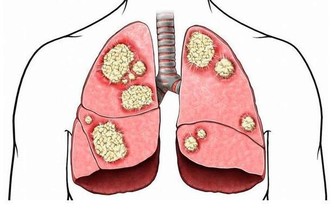

正常人的痰液為泡沫狀或黏液狀,當痰量增多則是病態現象,看痰的性狀提示的疾病:

清色或白色痰:為病毒感染居多,也可見於支氣管炎、肺炎初期;

金黃色濃痰:提示金黃色葡萄球菌感染;

鐵鏽色痰:為肺炎球菌肺炎的典型特徵;

黃綠色或翠綠色痰:提示銅綠假單胞菌感染;

痰白粘稠且呈絲狀:提示真菌感染;

粉紅色泡沫痰:提示肺水腫,見於心功能衰竭者;

痰惡臭:提示厭氧菌感染。

治療,乾咳可以適當服用止咳藥物,針對乾咳的藥物有福爾可定口服液、氫溴酸右美沙芬、枸櫞酸噴托維林等;咳痰不能服用止咳藥物,易存在痰液殘留加重感染,可服用祛痰藥物,讓痰液咳出,常用的祛痰藥物有:氯化銨、溴己新、氨溴索、乙酰半胱氨酸、羧甲司坦等。祛痰藥使用後可出現咳嗽加重,為排痰作用。